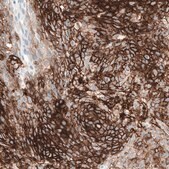

Anti-CD44 antibody produced in mouse

Prestige Antibodies® Powered by Atlas Antibodies, clone CL13319, purified by using Protein A, buffered aqueous glycerol solution

immunohistochemistry: 1:5000-1:10000